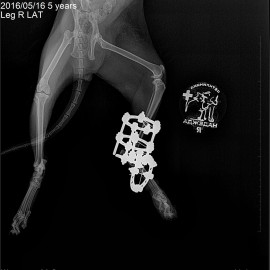

Наш пациент, кот, по кличке Архип.

Обратились к нам после автотравмы с жалобами на отсутствие опороспособности на правую заднюю лапу.

Было проведено рентгенологическое исследование.

Поставлен диагноз: перелом правой голени, вывих правого голеностопного сустава. Была проведена операция: остеосинтез правой голени, остеосинтез правого голеностопного сустава.

Снимок 3-4 после операции.